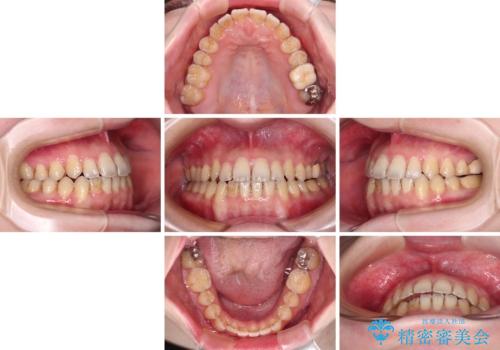

- インビザライン

- 1年3ヶ月

- 前歯の開咬を気にして来院された患者様です。

開咬の治療は、前歯を閉じるように動かすとともに、上下臼歯を圧下(骨内にめり込ませる)させることで進めて行きます。

インビザラインは臼歯の圧下を効果的に行えるため、インビザラインを用いて矯正治療を行うこととしました。